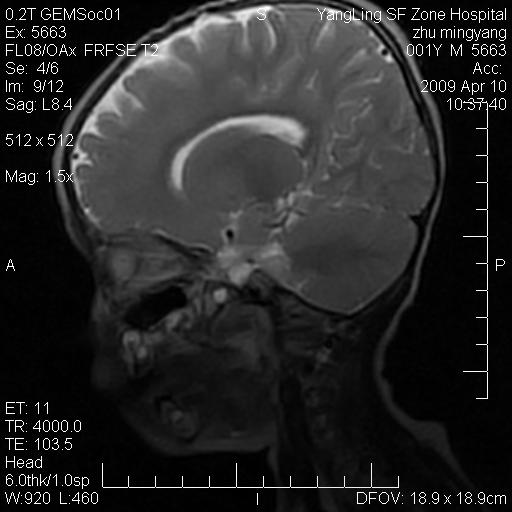

患者:1岁半,两天前外伤收住我院,ct检查小脑占位

考虑星形细胞瘤,建议增强

髓母细胞瘤或血管母细胞瘤,增强后可以鉴别;影像资料见 <。鱼博浪老师的《中枢神经系统ct与mr鉴别诊断》 小脑部肿瘤章节。

髓母细胞瘤或血管母细胞瘤!支持!

支持考虑髓母细胞瘤

考虑----髓母细胞瘤可能性大

考虑髓母细胞瘤或室管膜瘤。

支持髓母细胞瘤。

考虑髓母细胞瘤。

考虑髓母细胞瘤或星形细胞瘤

考虑髓母细胞瘤.

小脑肿瘤.考虑髓母细胞瘤可能.

就病灶部位及临床资料首先考虑髓母.